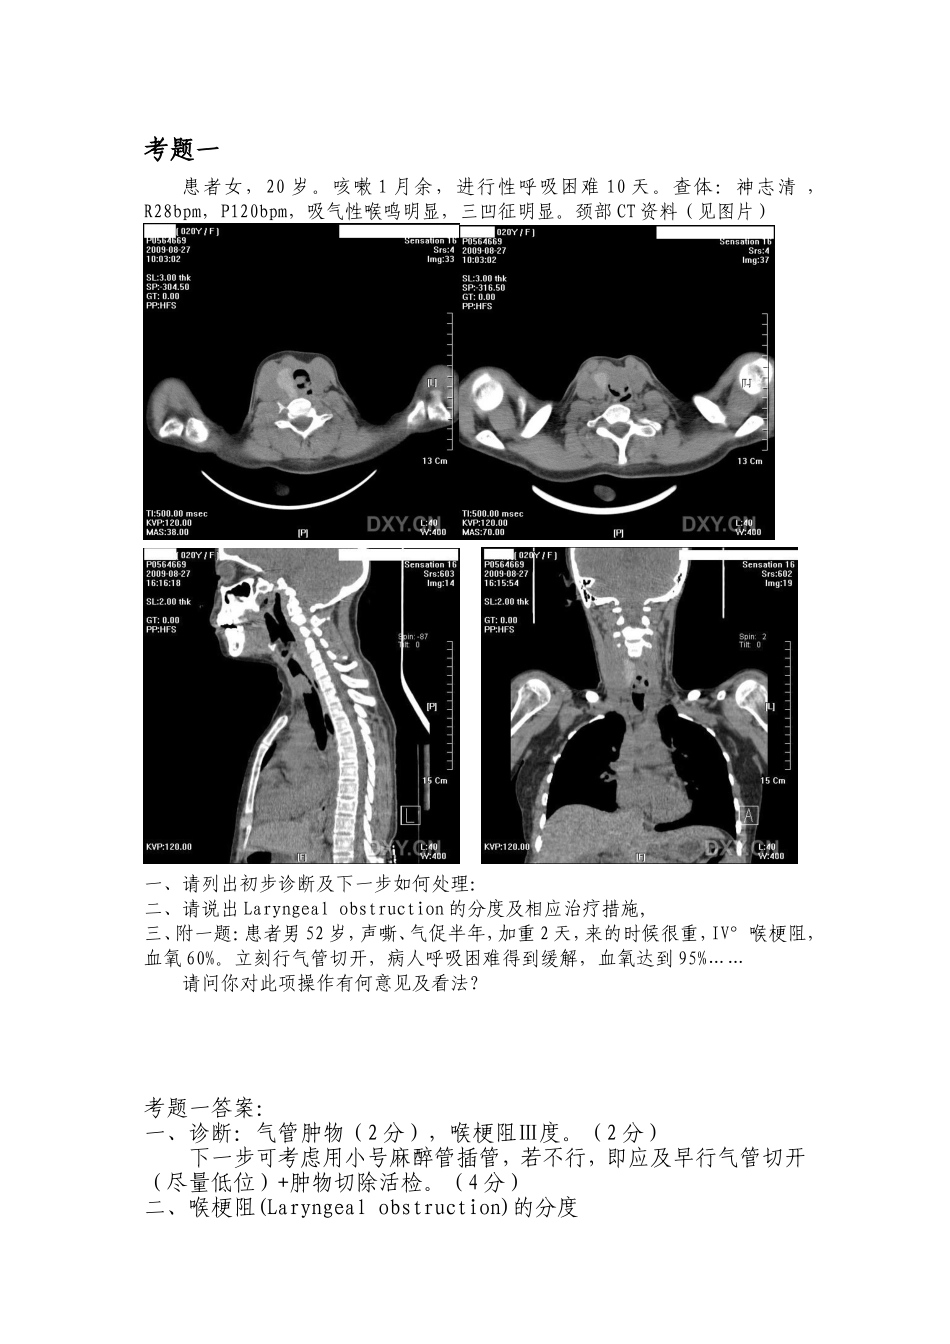

考题一患者女,20岁。咳嗽1月余,进行性呼吸困难10天。查体:神志清,R28bpm,P120bpm,吸气性喉鸣明显,三凹征明显。颈部CT资料(见图片)一、请列出初步诊断及下一步如何处理:二、请说出Laryngealobstruction的分度及相应治疗措施,三、附一题:患者男52岁,声嘶、气促半年,加重2天,来的时候很重,IV°喉梗阻,血氧60%。立刻行气管切开,病人呼吸困难得到缓解,血氧达到95%……请问你对此项操作有何意见及看法?考题一答案:一、诊断:气管肿物(2分),喉梗阻Ⅲ度。(2分)下一步可考虑用小号麻醉管插管,若不行,即应及早行气管切开(尽量低位)+肿物切除活检。(4分)二、喉梗阻(Laryngealobstruction)的分度喉阻塞(laryngealobstruction)是喉部或邻近器官的病变使喉部气道变窄以致发生呼吸困难。其并非一独立的疾病,而是一组症候群。由于喉阻塞可引起缺氧,如处理不及时可引起窒息,危及病人生命。由于发病急、缓不同,喉阻塞分急性和慢性两类。根据病情轻重,喉阻塞可分为四度一度:平静时无症状,活动时有轻度吸气性困难。(1分)二度:安静时有轻度吸气性呼吸困难,活动时加重,但不影响睡眠和进食,缺氧症状不明显。(1分)三度:吸气期呼吸困难明显,喉鸣声较响,胸骨上窝、锁骨上窝等外软组织吸气期凹陷明显。因缺氧而出现烦躁不安、难以入睡、不愿进食。患者脉搏加快,血压升高,心跳强而有力,即循环系统代偿功能尚好。(1分)四度:呼吸极度困难。由于严重缺氧和体内二氧化碳积聚,患者坐卧不安,出冷汗、面色苍白或紫绀,大小便失禁,脉搏细弱,心律不齐,血压下降。如不及时抢救,可因窒息及心力衰竭而死亡。(1分)治疗喉阻塞能危及生命,必须高度重视,积极处理。应按呼吸困难的程度和原因,采用药物或手术治疗。一度:应明确病因,积极治疗。由喉部炎症引起者,应及时使用激素加抗生素,配合蒸气吸入或雾化吸入等。(1分)二度:积极治疗病因,严密观察病情变化,作好气管切开术的准备工作。如为异物,应立即取出;如为肿瘤,可考虑气管切开。(1分)三度:根据病因医疗条件,患者体质等全面衡量而决定。如为异物应及时取出,如为急性炎症,可先试用药物治疗,若观察未见好转或阻塞时间较长,全身情况较差时,应及早施行气管切开。因肿瘤或其他原因引起的喉阻塞,宜先行气管切开,待呼吸困难缓解后,再根据病因,给于其他治疗。(1分)四度:因病情危急,应当机立断,行紧急抢救手术。利用麻醉喉镜引导进行气管插管,或插入气管镜解救呼吸或行环甲膜切开。待呼吸困难缓解后再作常规气管切开术,然后再寻找病因进一步治疗。(1分)三、慢性缺氧患者可能在缺氧改善后因突然高氧状态导致呼吸抑制,注意在充分准备好呼吸机或者抢救措施情况下再进行气管切开。(4分)考题二病例,男,64岁,因声音嘶哑3个月,加重伴呼吸困难2天来院求治,既往10×30年吸烟史,一、请列出初步体格检查及辅助检查内容?-------------------------------------------------患者纤维喉镜显示如下:患者CT显示如下二、请列出初步诊断,以及下一步诊疗措施。-______________________________________________________三、请列出喉癌的分型及临床表现课题二答案一、常规咽喉部体格检查,包括口咽部检查(3分),间接喉镜看咽喉部(3分),声带及其动度(2分),梨状窝及会厌(2分),考官充当SP,考核操作技能二、声门型喉癌?(2分)进行电子喉镜或者纤维喉镜检查并取活检,待病理报告出来后,收入院。(2分)三、1.声门上型:不适感或异物感,痰中带血,声嘶、呼吸困难等。易颈部淋巴结转移。(2分)2.声门型:前、中1/3处较多,早期症状为声嘶,后期呼吸困难。不易转移。(2分)3.声门下型:早期症状不明显,常规喉镜检查不易发现。可侵及甲状腺,也可侵犯食管前壁。气管前或气管旁淋巴结转移。(2分)考题三患者男,23岁,反复左鼻塞、脓涕、头痛2+年,加重伴发热5天就诊。头痛表现为晨起轻午后重。检查见左中鼻道可见脓性分泌物。请问:一、鼻部常规体格检查及辅助检查。---------------------------------------------------------患者鼻内窥镜、CT所见如图:二、诊断及下...